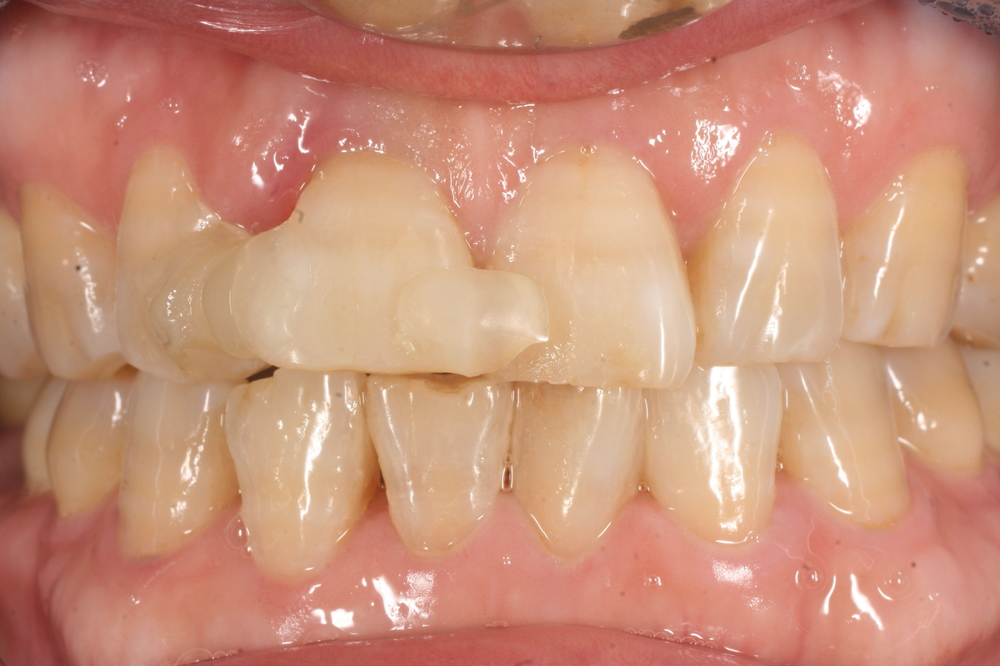

このように歯が割れている場合、まずは歯を保護するための応急処置を行います。

隣の歯と接着剤で一時的に固定し、痛みやぐらつきを抑えた状態で精密検査を進めました。

治療後は仮歯を経て、最終的に自然な色調のセラミッククラウンを装着し、

周囲の歯と調和した仕上がりになりました。